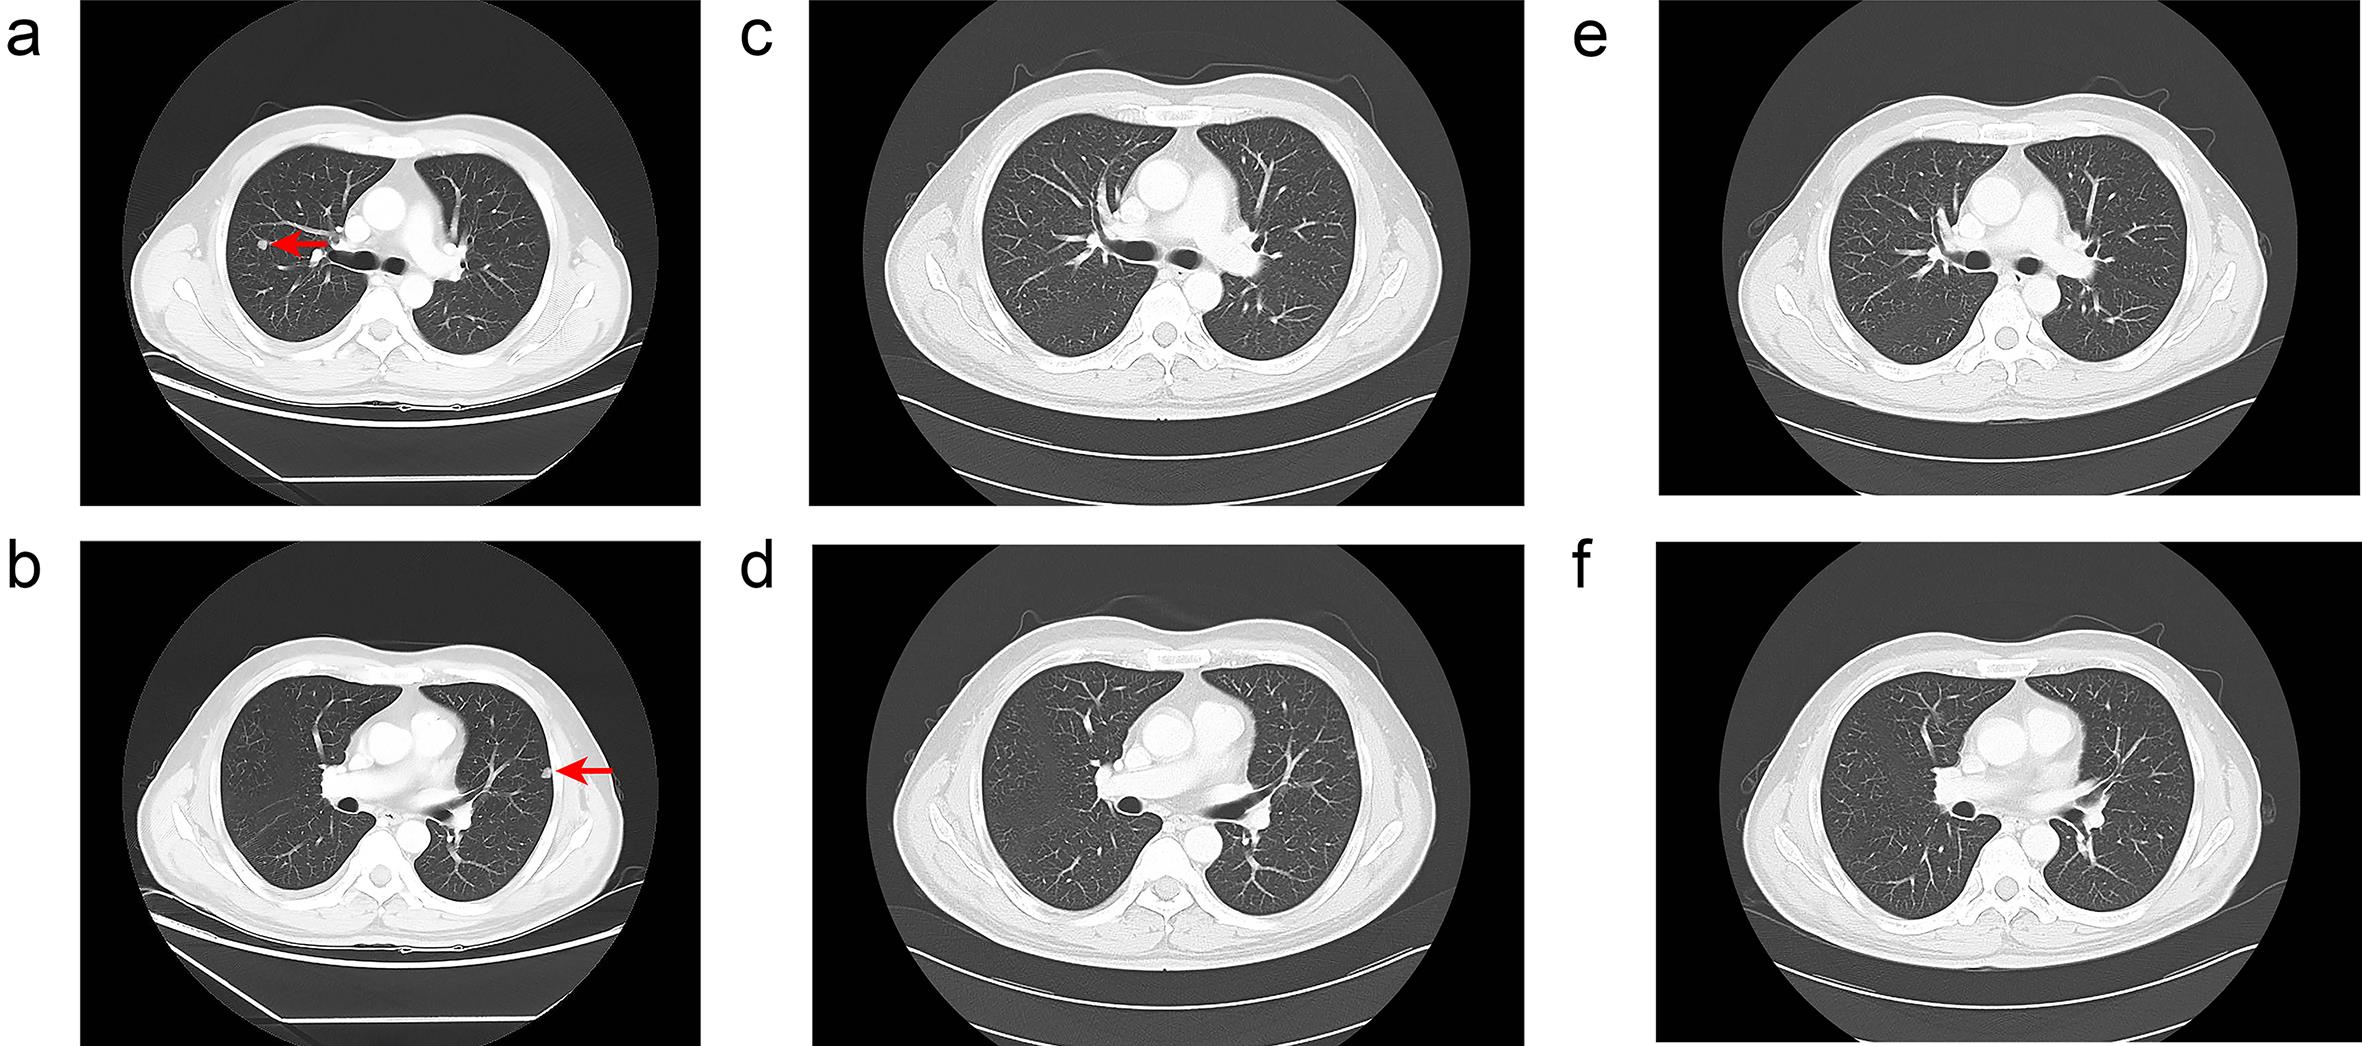

A 46-year-old Chinese male was admitted to our hospital with severe abdominal pain that had persisted for one day. The patient had a chronic hepatitis B viral infection and had not received any treatment over the past two decades. Physical examination showed no abnormalities. The patient’s Eastern Cooperative Oncology Group performance status score was 0. Serum alpha-fetoprotein level exceeded 2,000 ng/mL, and the level of protein induced by vitamin K absence or antagonist-II was 10,730 ng/mL. Enhanced computed tomography revealed two large nodular tumors located in the upper and lower segments of the right posterior lobe of the liver. The largest tumor measured 9.3 × 5.2 × 8.1 cm. Part of the tumor protruded beyond the liver surface and extended into the left lower quadrant. Hypodense areas within the tumor suggested liquefaction necrosis due to rupture and hemorrhage (Fig. 1a and b). The intrahepatic tumor burden exceeded 60% of the total liver volume. Multiple bilateral pulmonary metastases were also detected, with the largest lesion measuring 0.8 × 0.7 × 0.8 cm (Fig. 2a and b).

Computed tomography images of the lung showing pulmonary metastases at different time points.

Fig. 2  Computed tomography images of the lung showing pulmonary metastases at different time points.

(a, b) November 2, 2023. The red arrows indicate metastatic tumors. (c, d) January 18, 2024. No pulmonary metastases were detected. (e, f) May 10, 2024. No pulmonary metastases were detected.

After three months of treatment, enhanced computed tomography revealed no signs of tumor progression. According to RECIST 1.1,7 the intrahepatic tumors exhibited a partial response (Fig. 1e and f), and the bilateral lung metastases showed a complete response (Fig. 2c and d). After seven months, the patient returned for follow-up, and complete response status was maintained (Figs. 1g and h, 2e and f). The levels of alpha fetoprotein and protein induced by vitamin K absence or antagonist-II decreased to normal levels (Fig. 3a and b, Table S1). In total, the patient received nine cycles of tislelizumab and seven months of lenvatinib. The patient continues to undergo regular monthly blood counts and liver function tests to monitor for adverse events. No significant immune-related adverse effects, including liver dysfunction, hypertension, or proteinuria, were observed during treatment. Follow-up is ongoing (Fig. 4).